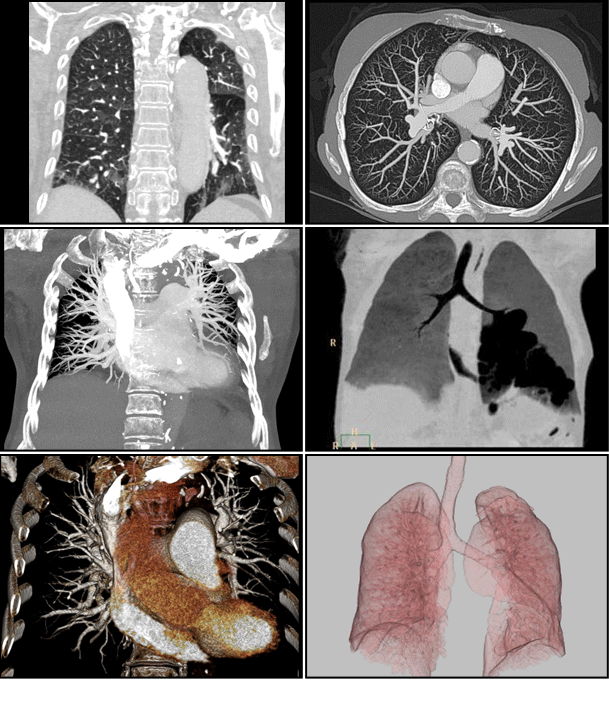

• 3차원 흉부CT

심장CT